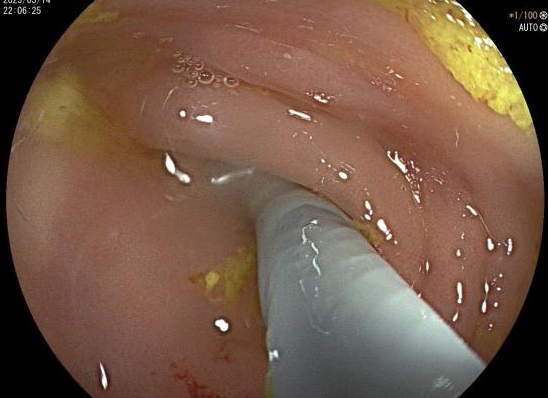

山东省立三院消化内科内镜逆行阑尾炎治疗术阑尾炎不开刀也能治

图片尺寸1336x750